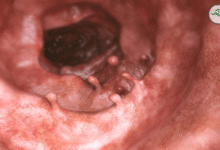

تشخیص پولیپ معده

تشخیص پولیپ معده معمولاً در طول آندوسکوپی فوقانی انجام می‌ شود، که در آن یک دوربین انعطاف‌ پذیر وارد معده می شود و امکان مشاهده پوشش معده و هرگونه پولیپ در آن را فراهم می‌ کند. متخصصان، پولیپ‌ ها را بر اساس اندازه، تعداد، شکل و محل قرارگیری ارزیابی می‌ کنند. همچنین در صورت مشاهده پولیپ در طی آندوسکوپی، از بافت آنها نمونه برداری می شود تا نوع پولیپ و خوش خیم، پیش سرطانی یا بد خیم بودن آنها مشخص شود. در اغلب موارد برای تشخیص و ارزیابی پولیپ های معده تصویربرداری استفاده نمی شود، مگر اینکه پولیپ بسیار بزرگ باشد.